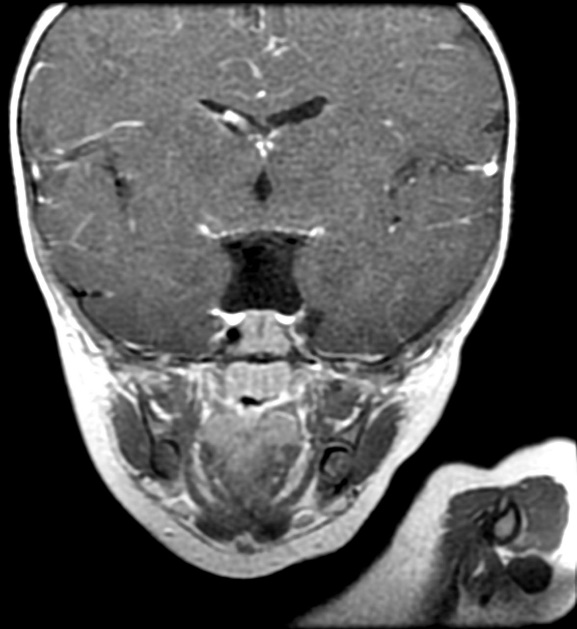

MRI findings showed the lack of the normal flow void of the left internal carotid canal and the first part of the left middle cerebral artery (Figures 1 and 2). The pituitary gland is flat. No evident anterior or posterior pituitary gland tissue or pituitary stalk is observed. The pituitary gland's strong posterior signal is not detected in situ or

ectopic. The left medial cerebral artery originates within the posterior circulation, and the left internal carotid artery cannot be seen. No intra, supra, retro or parasellar masses. Normal MRI appearance of the optic chiasm and corpus callosum. Otherwise, normal MR appearance of the brain parenchyma with no definite focal lesions. Diagnosis of congenital panhypopituitarism associated with agenesis of ICA was made.

a)

b)

c)

d)

Figure 2. a-c) show coronal MRI brain images, and d) is a view in which the left midcranial artery is coming from the posterior circulation and the left internal carotid artery is not visible (agenesis).